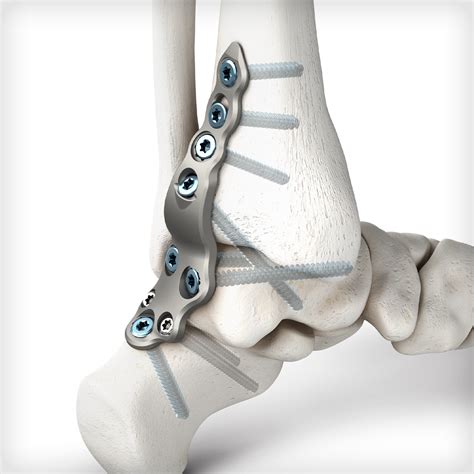

Ankle Fusion Procedures work by removing the damaged cartilage from the joint surfaces of the talus (the top bone of the foot) and the tibia (the shin bone). Once the cartilage is removed, the surgeon uses metal hardware, such as plates, screws, or rods, to hold these two bones together in a fixed position. Over the course of several months, the body naturally heals by bridging these bones with new bone tissue, creating a single, solid bone structure. The primary goal is to eliminate pain by preventing the grinding of bone-on-bone that occurs in advanced arthritis.